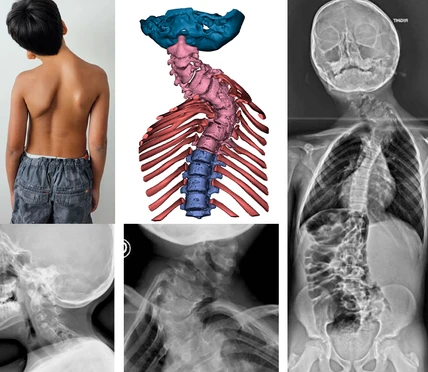

Escoliosis Congénita

Paciente de 12 años con diagnóstico de escoliosis congénita desde la infancia. A lo largo de los años, la curvatura de la columna progresó, afectando su postura y calidad de vida.